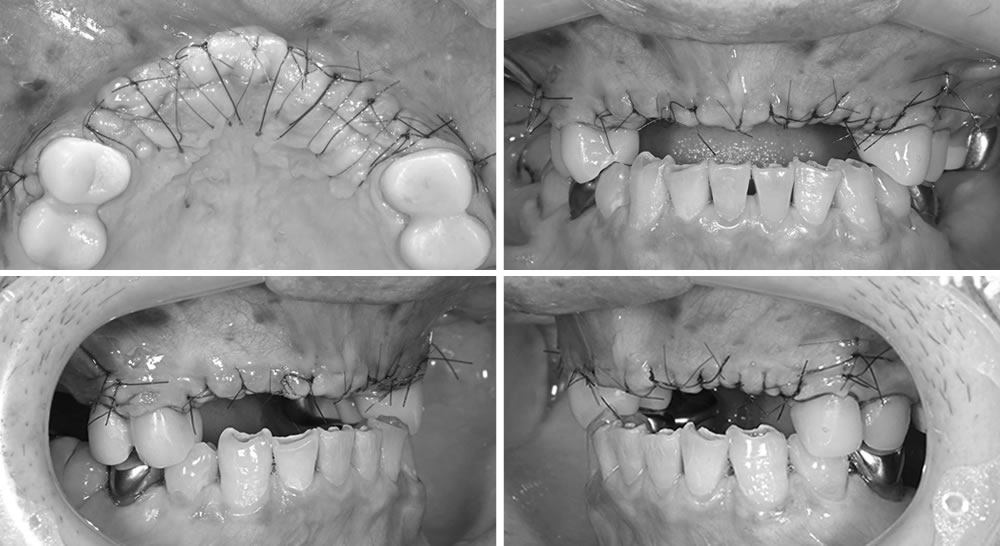

ナイロンの糸を用いて縫合、閉創を行いました。

上顎前歯部分と同時に左下奥歯にもインプラントを1本埋入し、縫合、閉創を行いました。